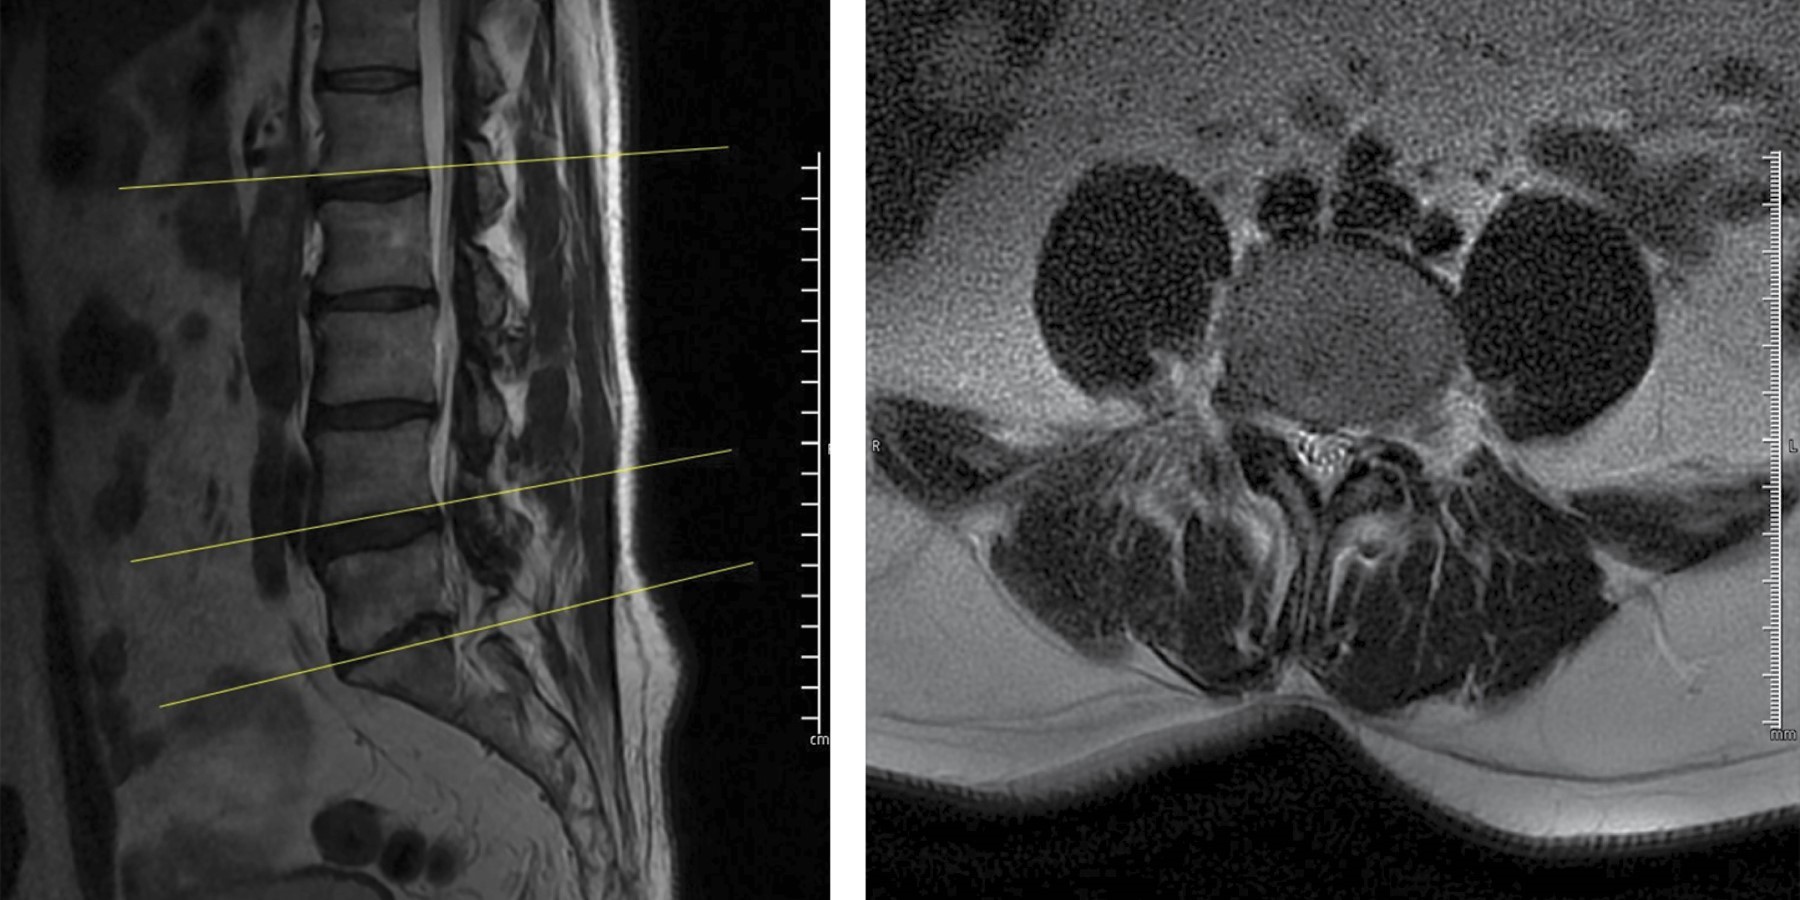

Se solicitó resonancia magnética simple de columna lumbosacra (Figuras 1 y 2), encontrando hernia discal extraforaminal L4-L5 derecha. Se decidió infiltración foraminal por la intensidad del dolor, sin embargo, no presentó mejoría, por lo que se decidió realizar microdiscectomía tubular tres días después. Se solicitaron estudios de laboratorio preoperatorios en los que se reportó leucocitos de 4.8 × 103 cel/mm3 con 44% de neutrófilos, proteína C reactiva (PCR) de 1.5 mg/l, velocidad de sedimentación globular (VSG) de 7 mm/h.

Después de realizar la microdiscectomía tubular, encontramos fragmento discal extraforaminal al igual que salida de material purulento (Figuras 3 y 4). Se tomaron muestras para cultivo, se realizó aseo quirúrgico y terminamos el procedimiento. El microorganismo aislado fue Staphylococcus aureus, por lo que se realizó interconsulta a infectología quien administró medicamento IV dirigido por antibiograma con ceftriaxona 2 gr IV cada 24 horas y daptomicina 500 mg IV cada 24 horas por seis semanas. Fue dado de alta a los cinco días después del procedimiento.